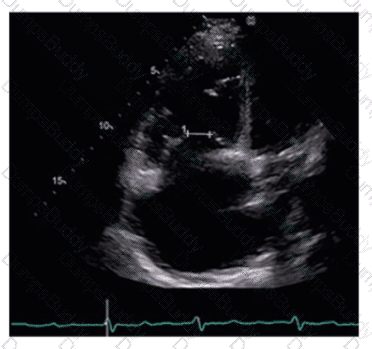

Which left ventricular regional wall segment is indicated by the arrow on this image?